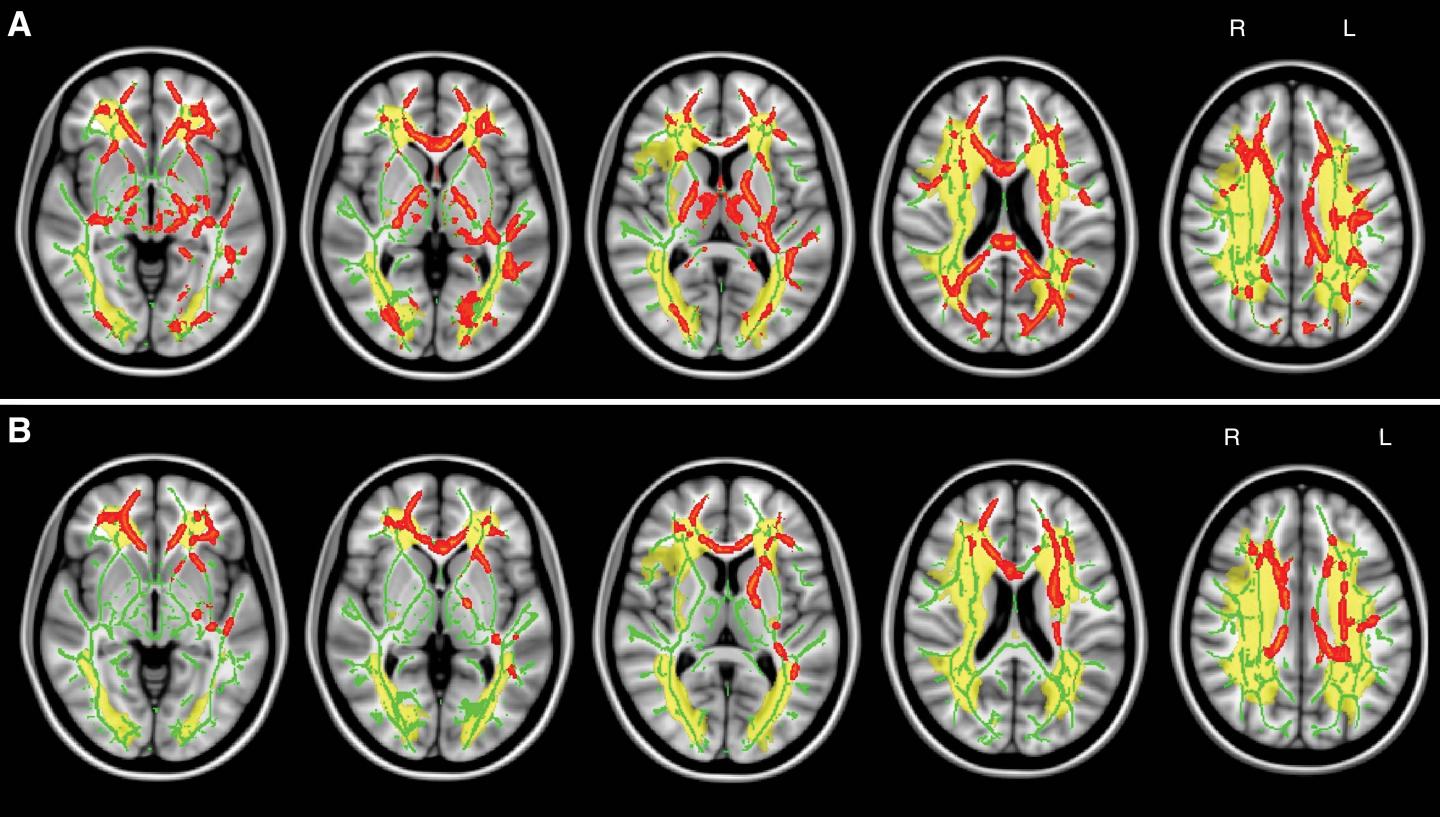

A biomarker that could predict and track vascular cognitive disorder on imaging exams has yet to be found, although MRI measurements of the brain's signal-carrying white matter are a promising area of research. Damage to the white matter can be assessed with diffusion tensor imaging, an MRI technique that provides two important measures of microscopic brain damage: mean diffusivity and fractional anisotropy. Increased mean diffusivity, which measures the movement of water through tissue, is particularly sensitive to the breakdown of nerve fibers in the brain and the protective coating around them.

For the new study, researchers assessed brain MRI and cognitive examination results from 108 patients with symptomatic carotid artery disease, a risk factor for vascular cognitive disorder. Of the 108 patients, 53 were cognitively impaired. Further analysis showed a clear correlation between cognitive performance and the presence of chronic vascular disease-related lesions within certain white matter tracts of the brain. White matter tract skeleton mean diffusivity showed the closest correlation with impaired cognitive performance, making it a promising tool for improved diagnostic accuracy of vascular cognitive disorder.

"Using standard clinical brain MRI, we found that microscopic damage of main white matter tracts allowed us to distinguish patients with symptomatic carotid artery disease and cognitive impairment from those who were cognitively intact," said the study's senior author, Dorothee P. Auer, Ph.D., from the University of Nottingham. "Our findings mean that a simple MRI test might improve the diagnostic work-up of people with suspected vascular cognitive disorder, and holds further promise to track progression of the disorder."

The results suggest that a key mechanism of vascular cognitive disorder is subcortical disconnection, a kind of breakdown of communication within the large-scale cognitive neural networks.